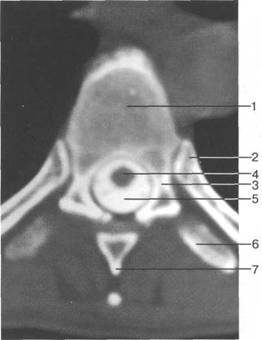

Ti

(lamina)

(uncus)